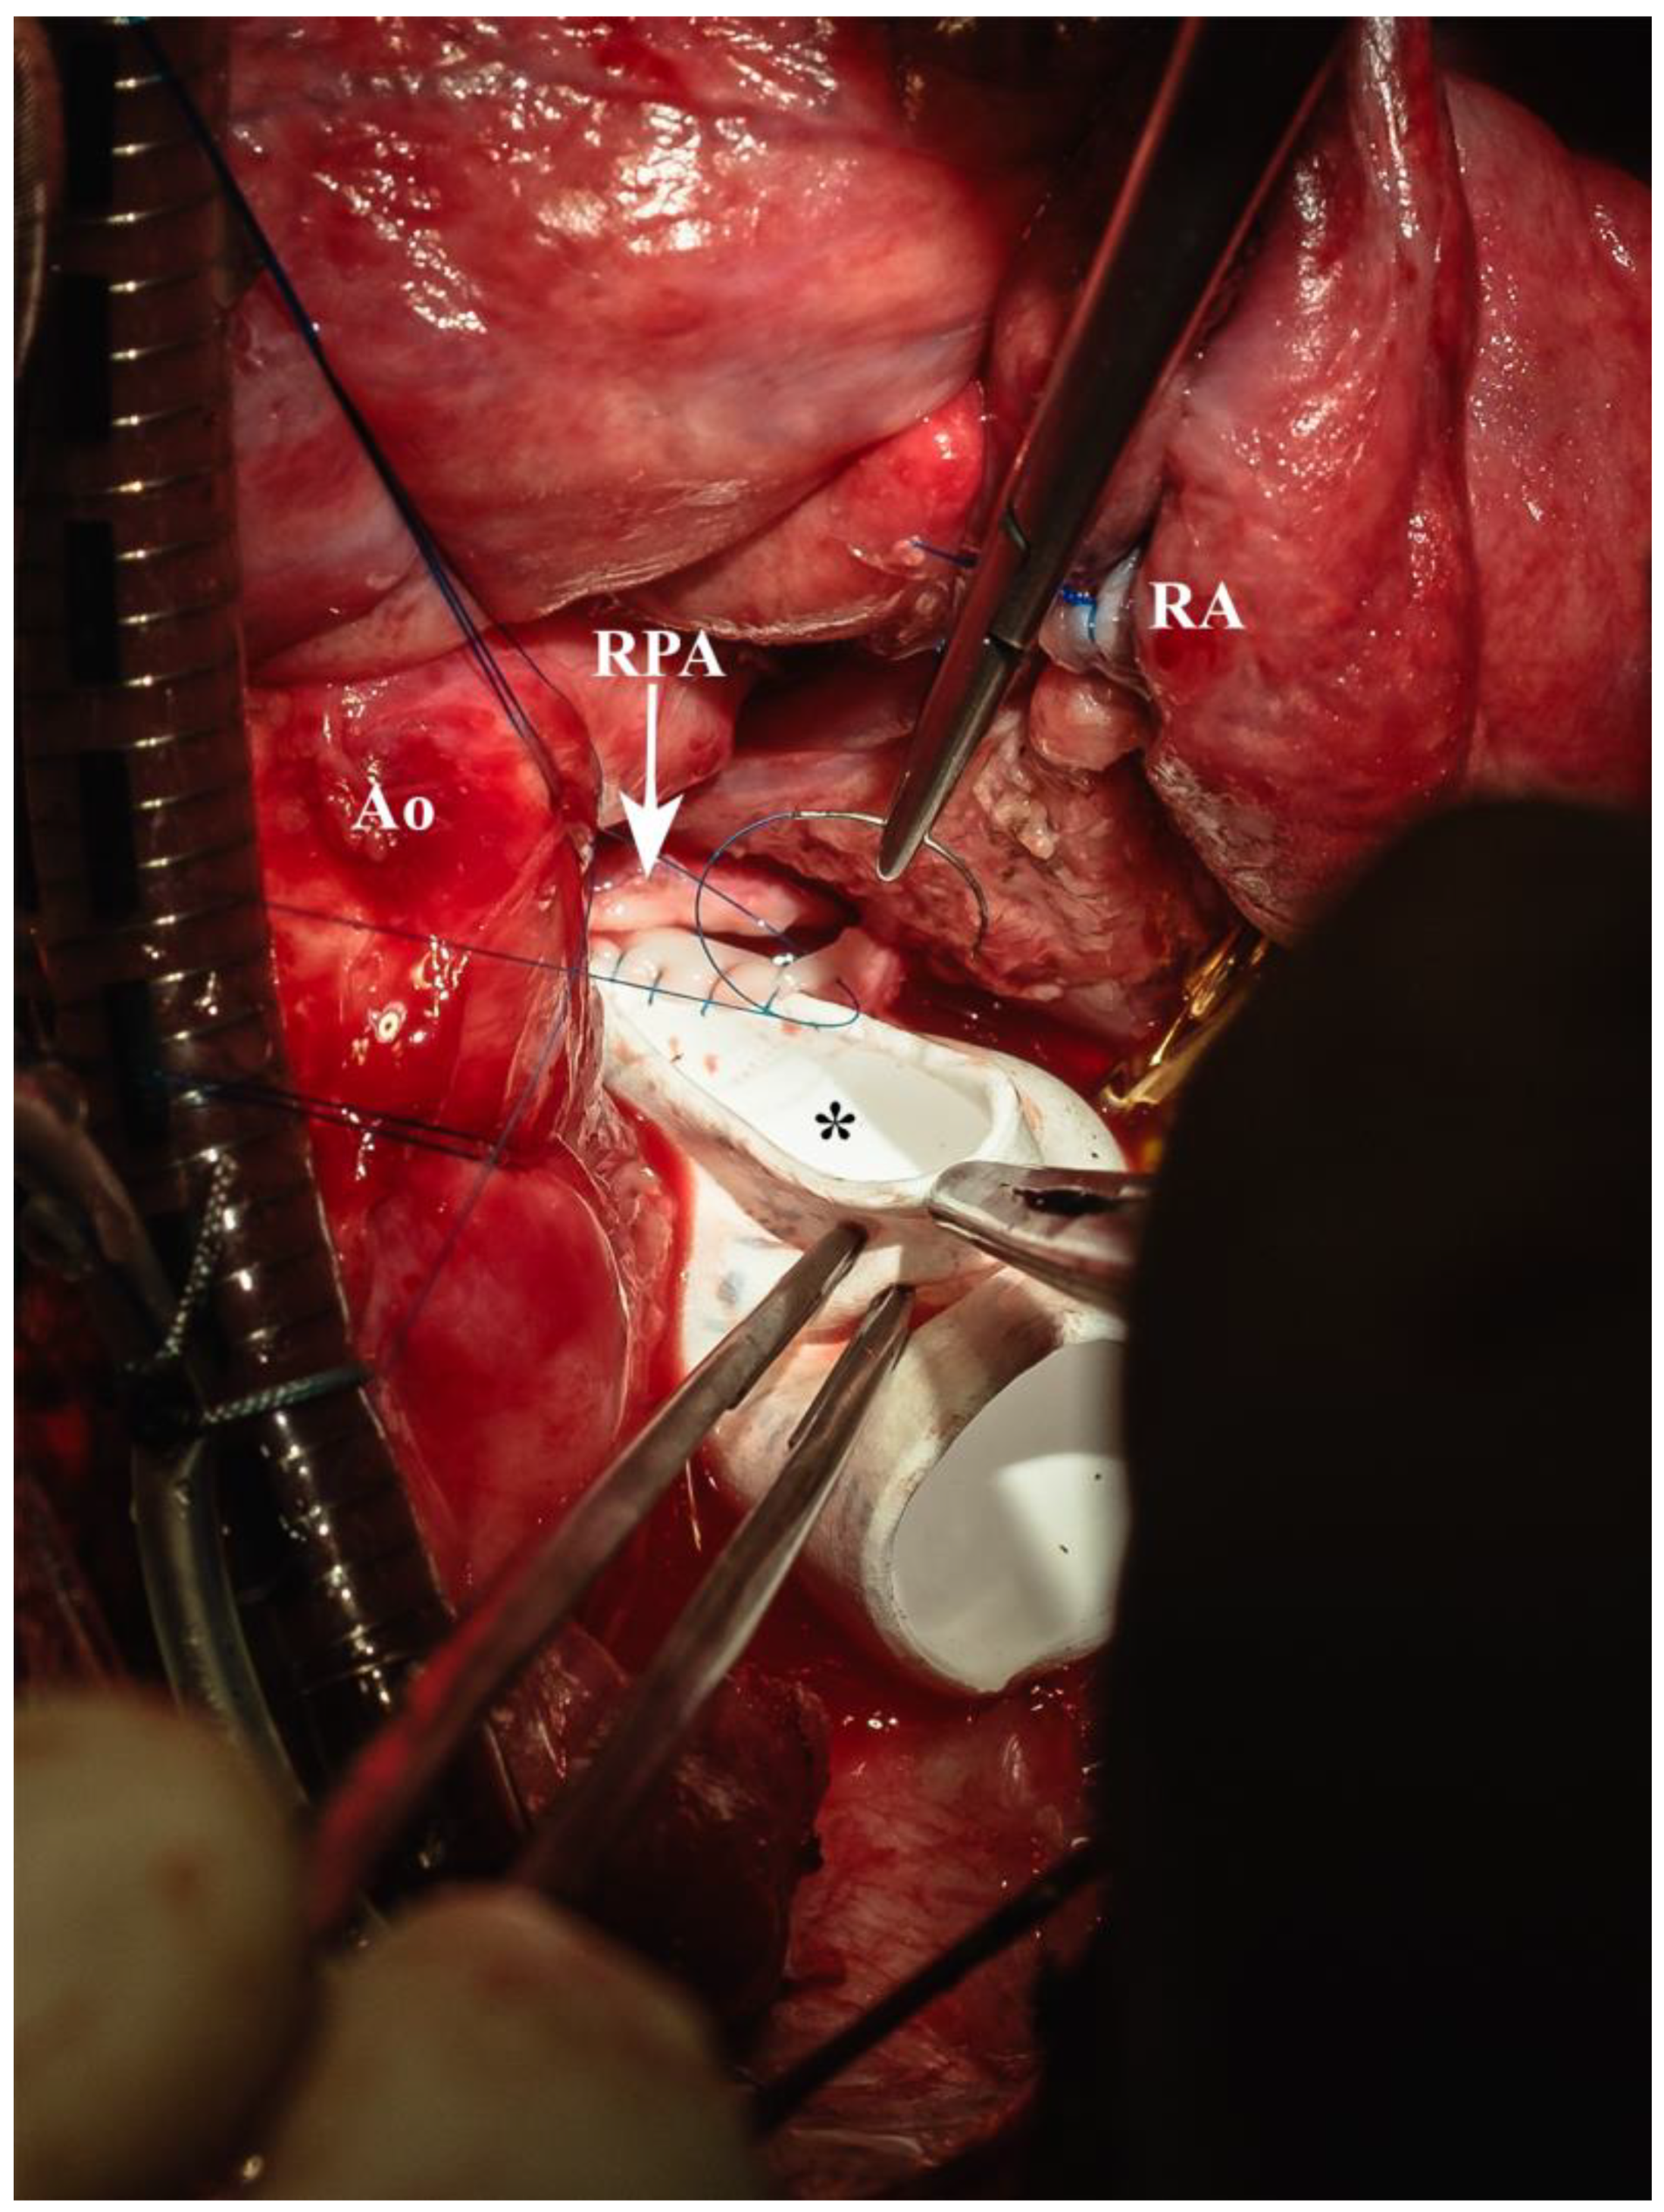

| Ao | aorta |

| RA | right atrium |

| RPA | right pulmonary artery |